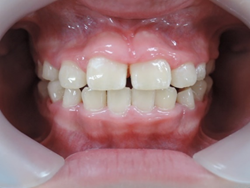

7歳2か月 女子

初診時乳臼歯にレジンを盛る事で咬み合わせの高さを治療していきます。

上顎から矯正装置を装着していきます。

初診時より1年6カ月後 終了時(8歳8か月)